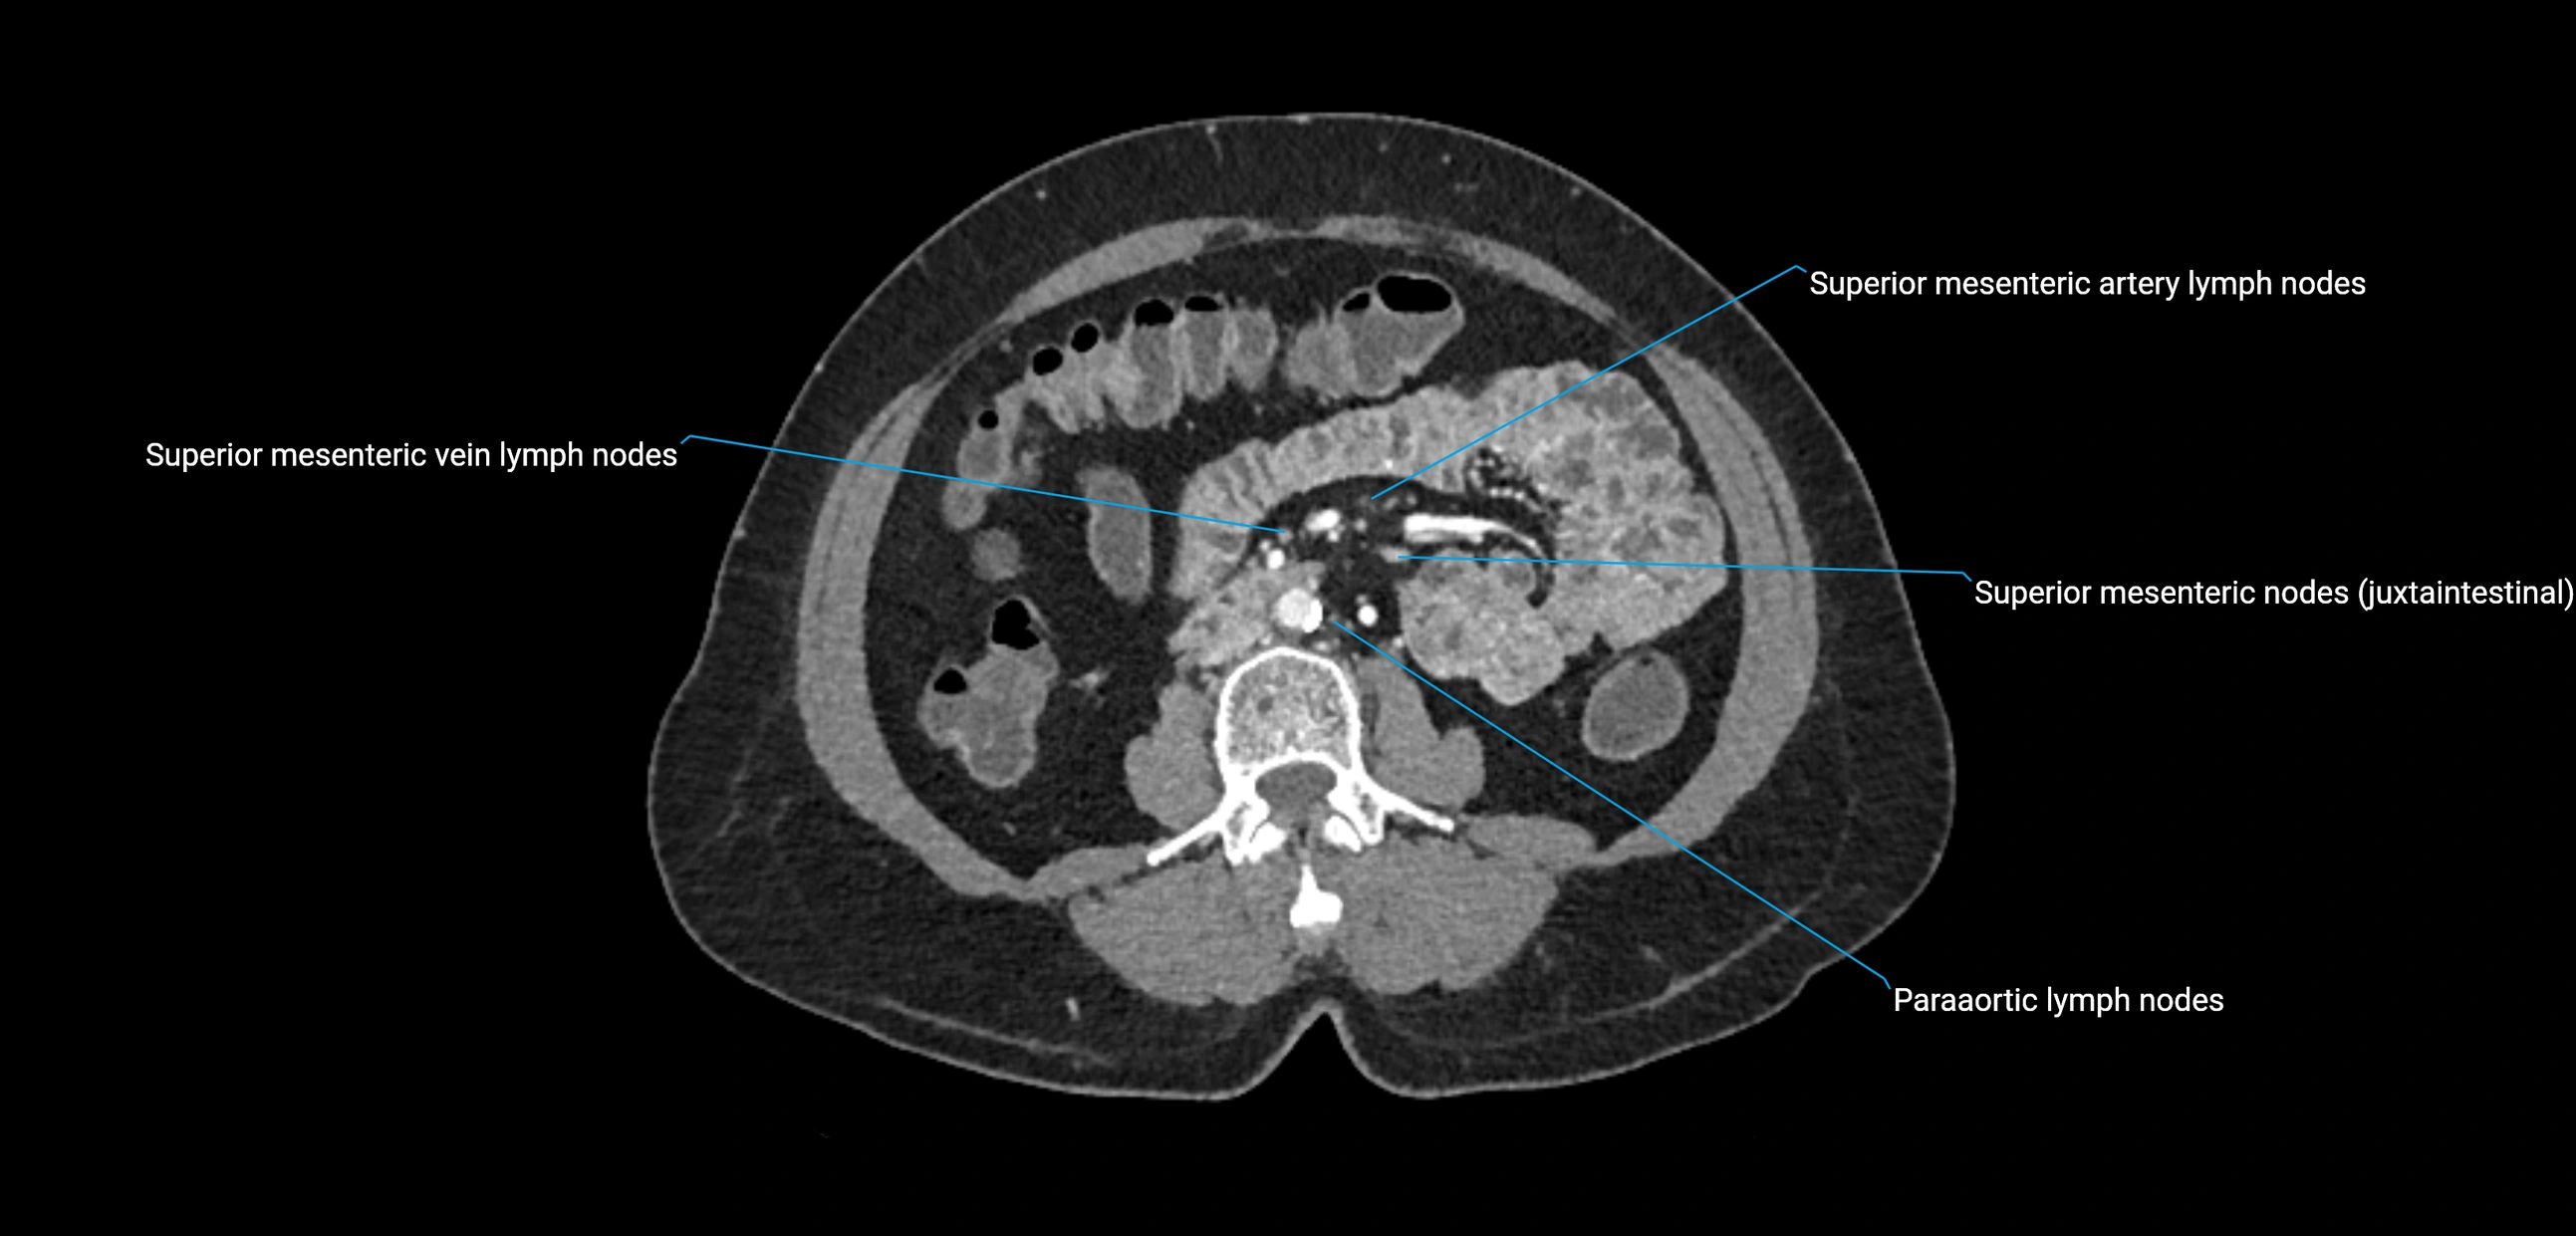

CT image

image